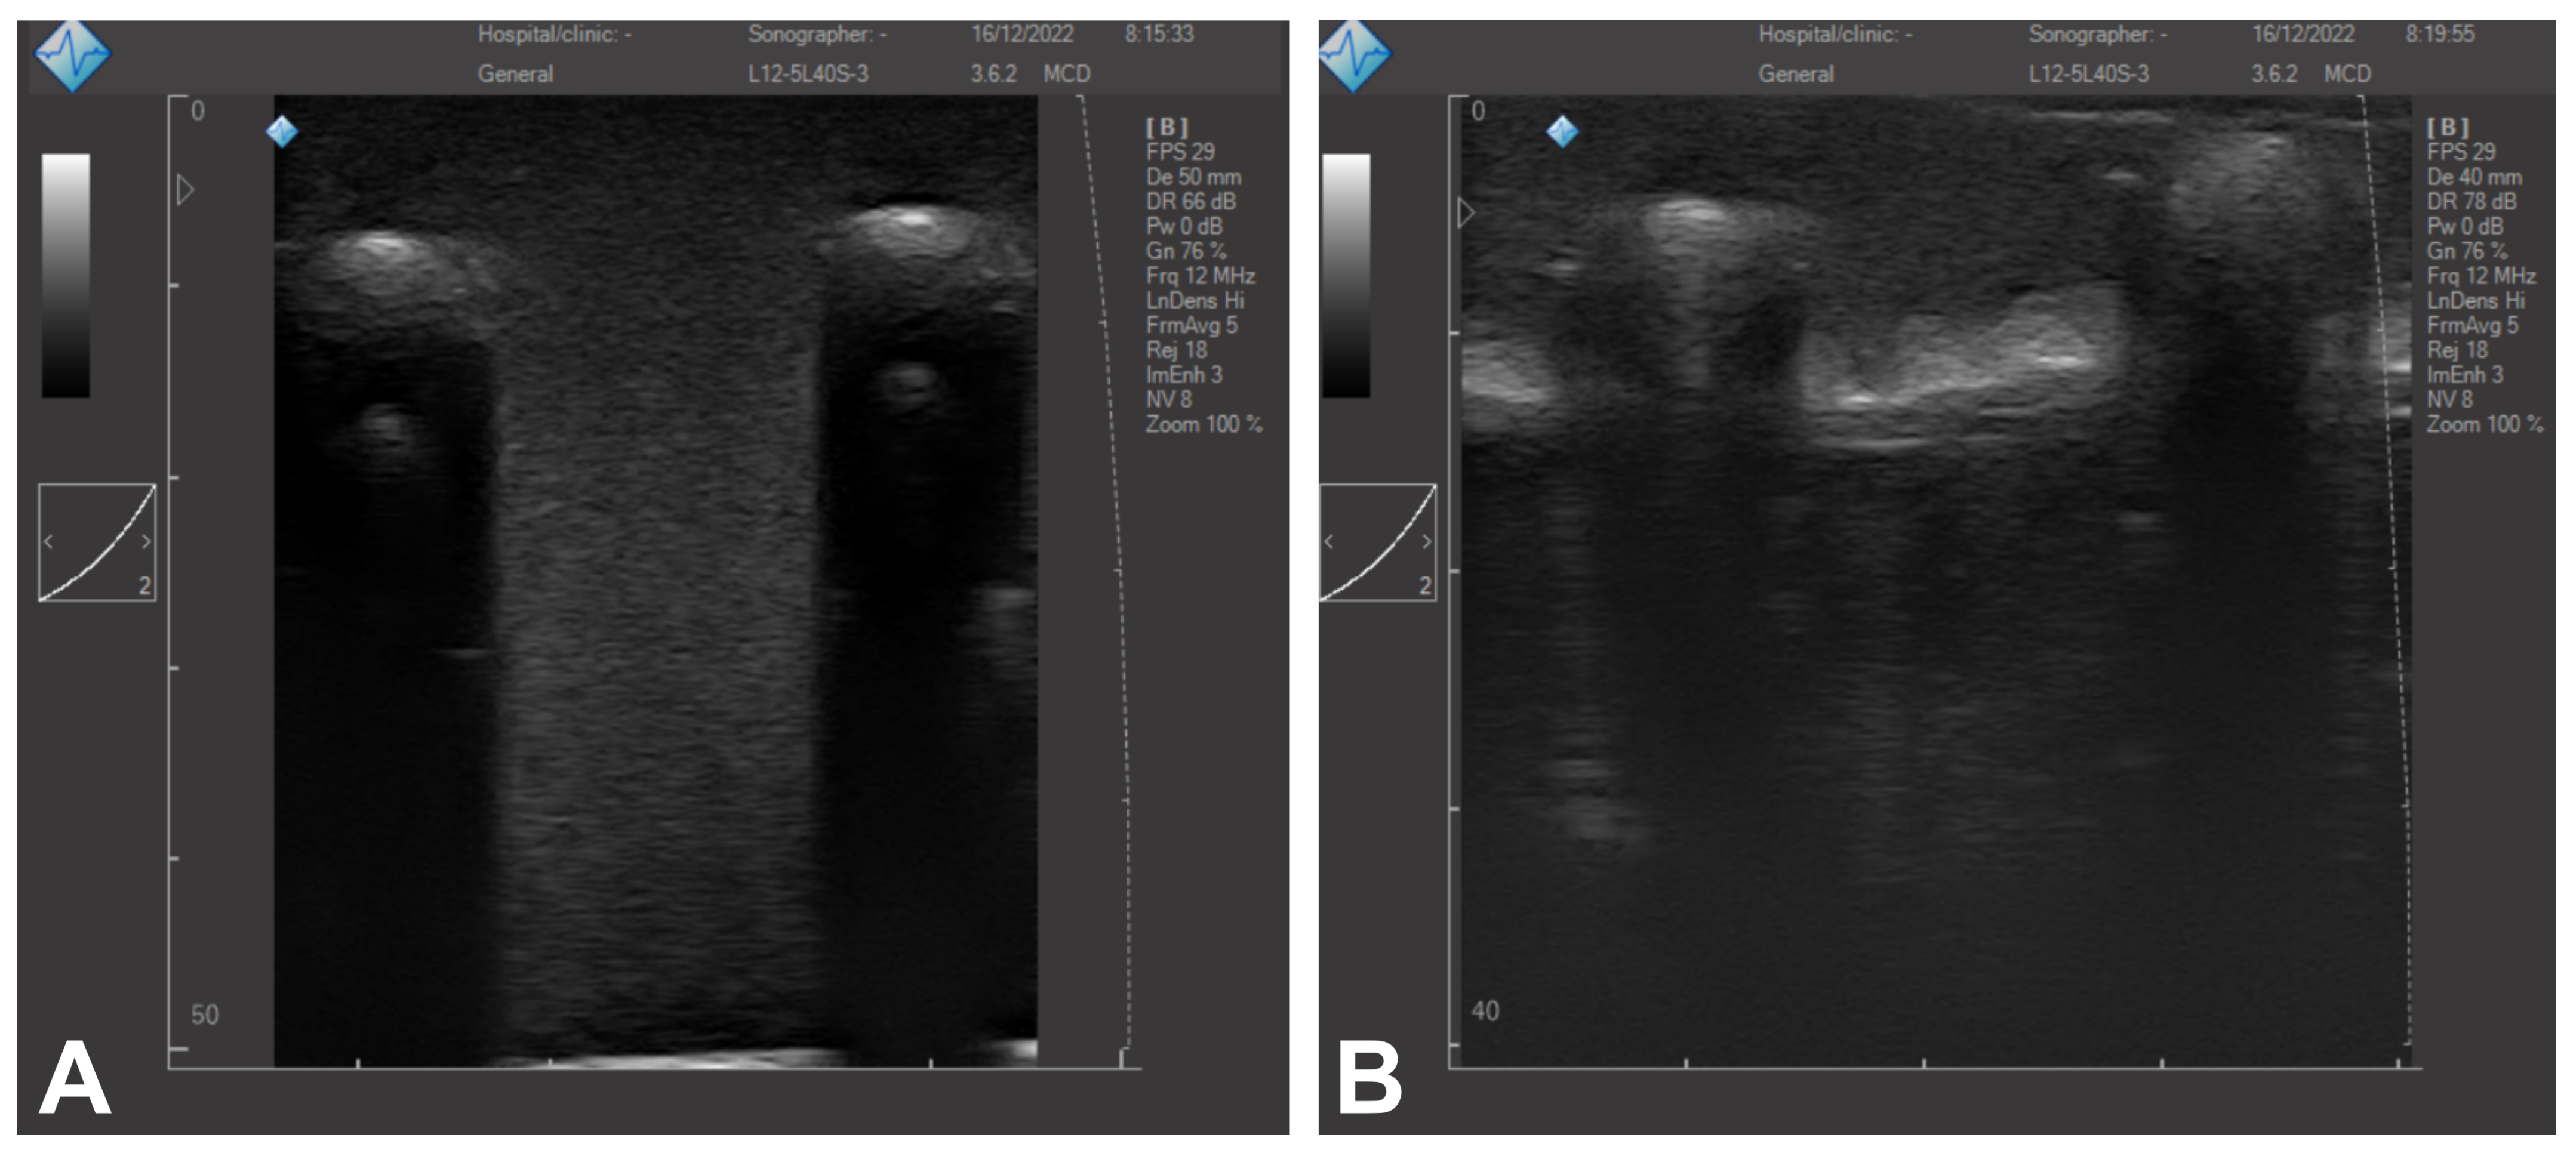

3.2. Ultrasound Imaging